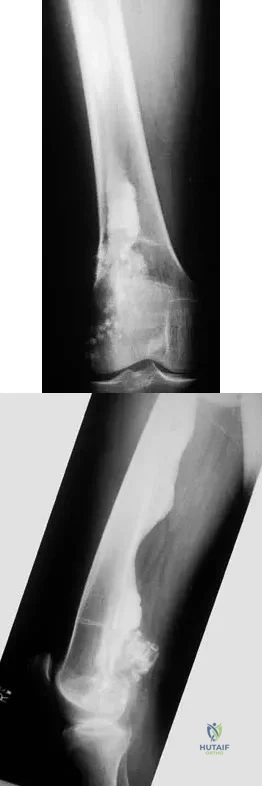

Figures 57a through 57c show the radiographs of a patient who has pain, discomfort, and a popping sensation localized to the posterior aspect of the knee after undergoing primary left total knee arthroplasty 6 months ago. Examination reveals that the patient is able to ambulate without a limp. There is no significant swelling, erythema, or effusion. Range of motion is 0 degrees to 115 degrees, and a palpable crepitation or snapping is detected at the posterior lateral joint line. What is the most likely diagnosis?

Explanation